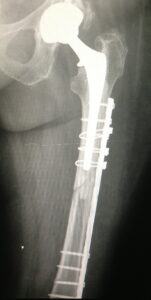

- Περιπροθετικό κάταγμα στην περιοχή του ισχίου στο επίπεδο του εμφυτεύματος.

- εσωτερική οστεοσύνθεση με πλάκα και αρκετή ελαστικότητα στο σύστημα.

- Ο ασθενής είναι σε πλήρη δραστηριότητα σε διάστημα δυόμισι μηνών μετά το κάταγμα.